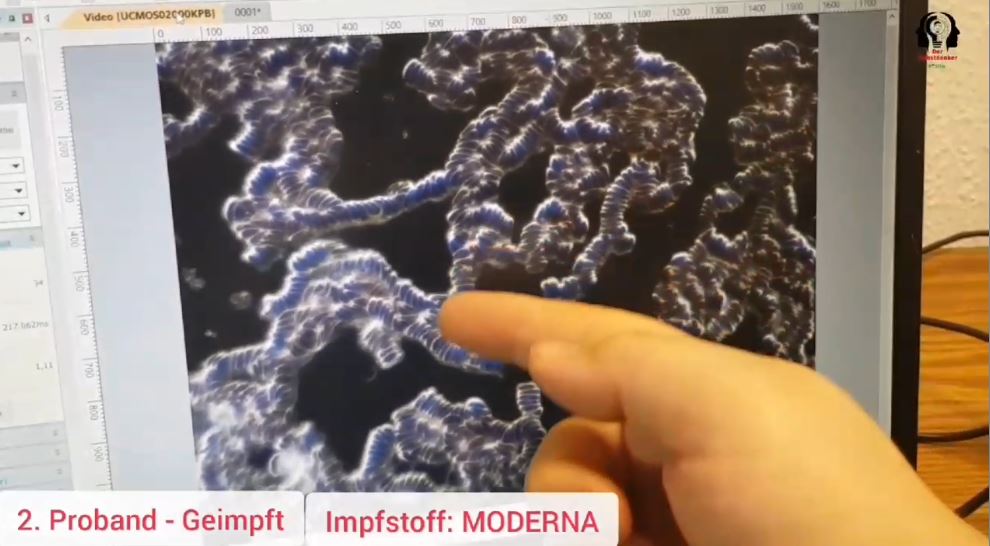

Impfschäden Schweiz Coronaimpfung,

[02/12/2021 11:07 A.M.]

https://t.me/Impfschaden_Corona_Schweiz/32666

Eine neue Meldung:

Ein Arzt in Sachsen hat am Montag 29.11. in seiner

Praxis zusammen mit einem Naturheilpraktiker und dem

Kanalbetreiber von “Der Selbstdenker” eine vergleichende

Blutuntersuchung von jeweils 4 Geimpften und 4

Ungeimpften unter dem Dunkelmikroskop

durchgeführt. Jedes Detail wurde gefilmt, um Transparenz

und Glaubwürdigkeit zu demonstrieren.

Ergebnis: Die Struktur und Beweglichkeit der

Blutkörperchen weisen signifikante Unterschiede auf; so

sehr dass es einem schlecht wird.

Bei den Ungeimpften haben die Blutkörperchen eine runde

und abgegrenzte Struktur, die je nach Lebensweise

Unterschiede aufzeigt.

Bei den Geimpften mit Biontech und Moderna sieht man im

Dunkelmikroskop, wie die Blutkörperchen zu einem

Breiartigen Cluster zusammen gepappt sind und fast keine

Beweglichkeit mehr zeigen. Die Aufnahme von Sauerstoff

ist damit signifikant reduziert und wenn sich die

Blutkörperchen nicht mehr bewegen können, sind auch die

Aufgaben im Organismus nicht mehr möglich. Der Arzt sagt

im Video (lange Version), dass damit auf Dauer ein

Sauerstoffmangel in sämtlichen Organen zu erwarten ist.